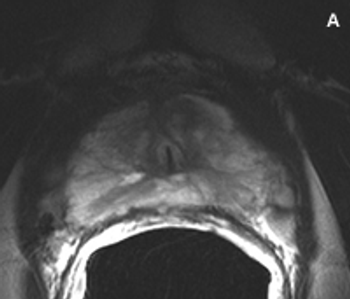

Image-guided intensity-modulated radiotherapy, high-intensity focused ultrasound, and cryotherapy are increasing the curative treatment options for men with prostate cancer. The problem is how to determine which patients are most suitable for these therapies.